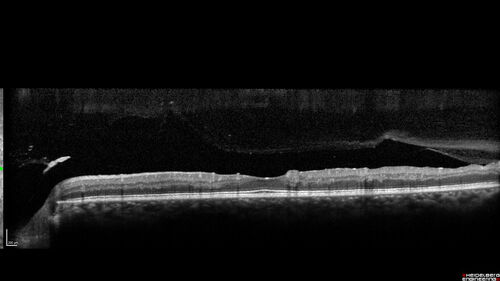

Severe Proliferative Diabetic Retinopathy and Good Vision

49 year old man with vision loss in the right eye for 2 weeks. VA 20/40 OD, 20/63 OS. DM x 15 years and HTN.